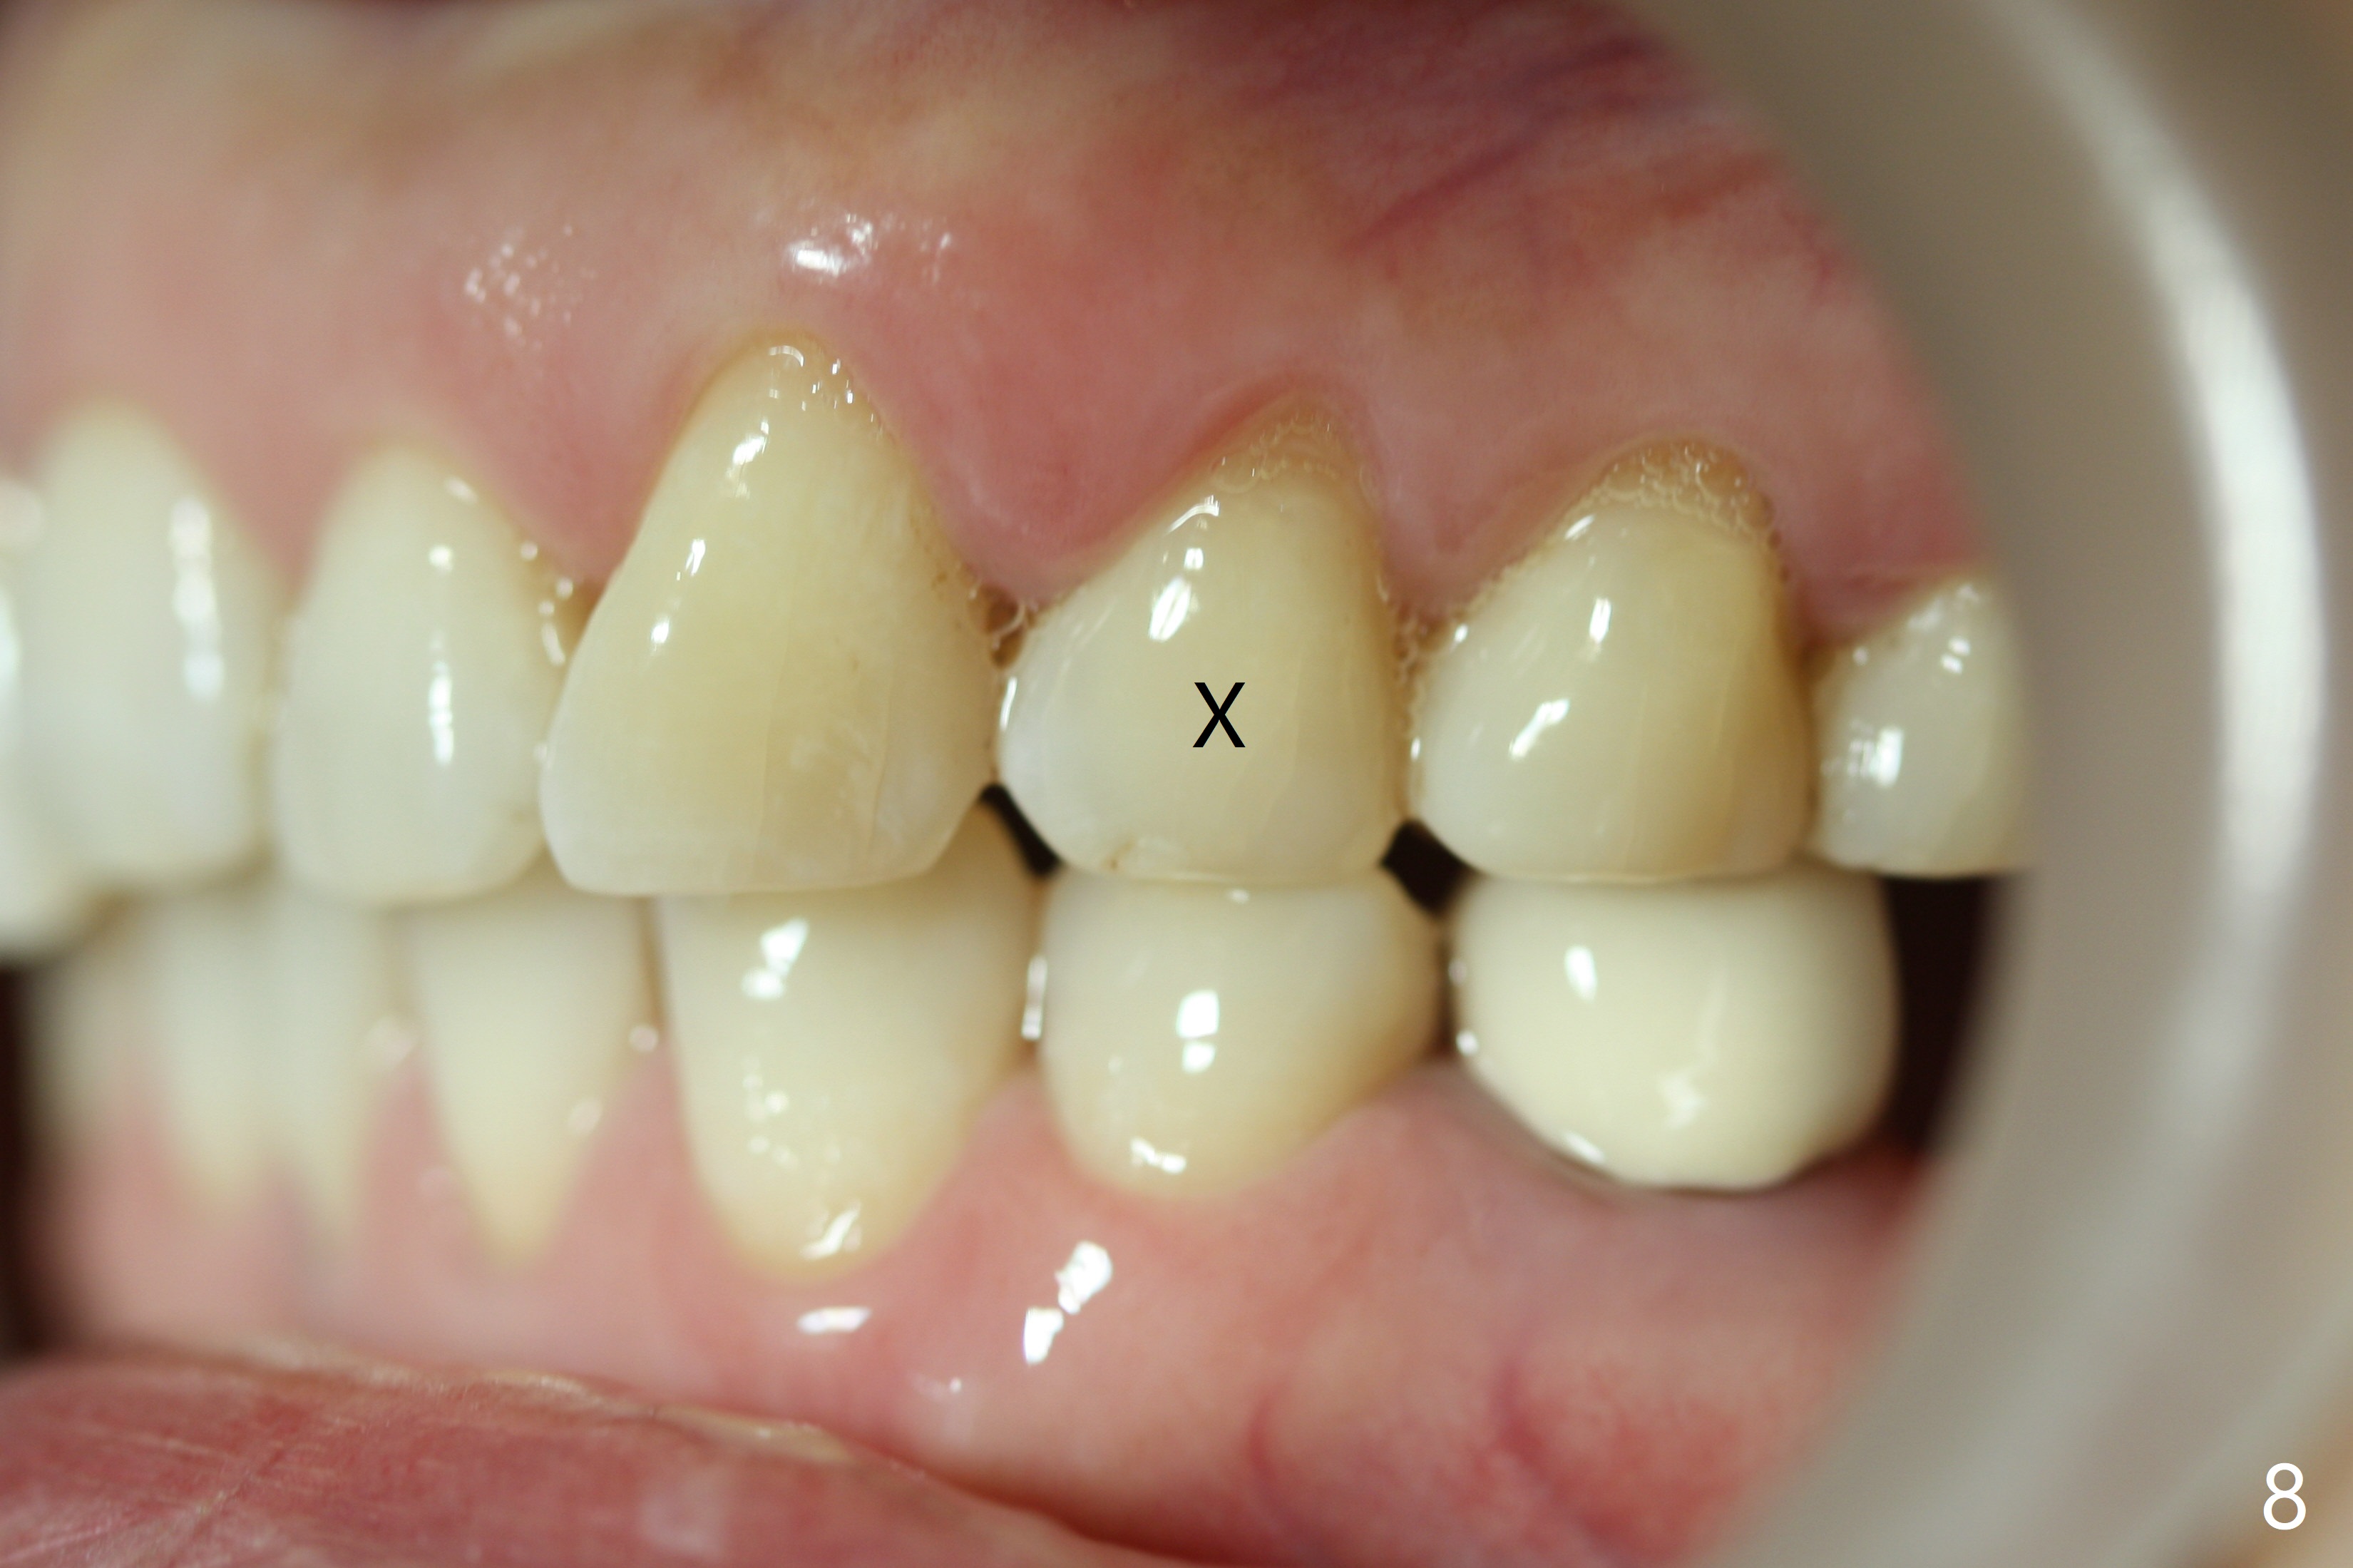

In addition, the upper dental midline deviates (Fig.2). It appears necessary to extract U4s (Fig.6,8: X) for realignment (Fig.9,11). When UR1 is intruded orthodontically (compare Fig.6,7 with 9) without increased mobility, it will be retained with lingual retainer. Otherwise it will be extracted for implant. Model surgery confirms the necessity of U4 extraction.